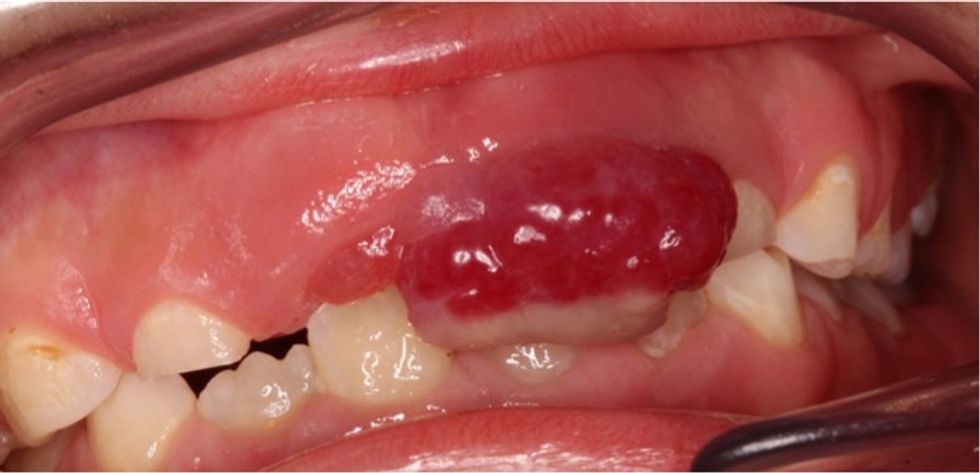

Granuloma piogjenike fillon të rritet si një rritje e vogël, me mish në lëkurë ose në mukozën. Zakonisht rritet shpejt dhe varion në madhësi nga disa milimetra në gjysmë centimetri, edhe pse kjo mund të ndryshojë gjithashtu. Një granulomë piogjene shpesh përshkruhet si një copë mishi i bluar. Ato mund të jenë rozë, të kuqe, kafe të kuqërremtë ose më mirë vjollcë, dhe shpesh kanë një bazë me luspa, të bardhë rreth fundit.

Kur formohen dhe kalon pak kohë, ato shpesh ngjiten në lëkurë si papilloma, por gjithashtu mund të ngjiten plotësisht drejtpërdrejt në lëkurë. Sipërfaqja e një granulome piogjene është e lëmuar, por gjithashtu mund të bëhet me gunga ose kore. Lezionet janë delikate, të ndjeshme, që rrjedhin, dëmtohen dhe rrjedhin gjak lehtësisht.